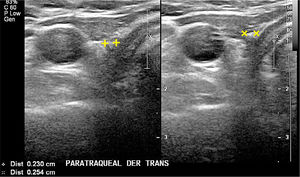

En el lecho tiroideo normal se identificará tejido hiperecogénico que corresponde a grasa; a la derecha entre la tráquea y la carótida común y a la izquierda entre la tráquea y la carótida común con mayor o menor presencia desde dorsal del esófago. Muchas veces vemos nódulos pequeños, hiperecogénicos, con sombra acústica, para y prelaríngeos, generalmente avasculares, que corresponden a granulomas calcificados en relación a material de sutura (Figura 10). En ocasiones estos granulomas alcanzan un mayor número y tamaño, pero generalmente hipo o avasculares.

Lecho post operatorio.

Cortes transversal cervical paratraqueal derecho, a dos niveles diferentes en el mismo paciente tiroidectomizado. No hay imagen de tejido tiroideo. Dos pequeñas estructuras hiperecogénicas, con sombra acústica posterior, con caracteres de nódulo calcificado, adyacentes a la tráquea.